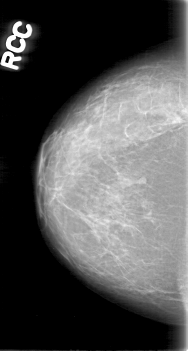

D_4080_1.RIGHT_CC

RIGHT_CC LINES 5251 PIXELS_PER_LINE 2806 BITS_PER_PIXEL 12 RESOLUTION 43.5 NON_OVERLAY